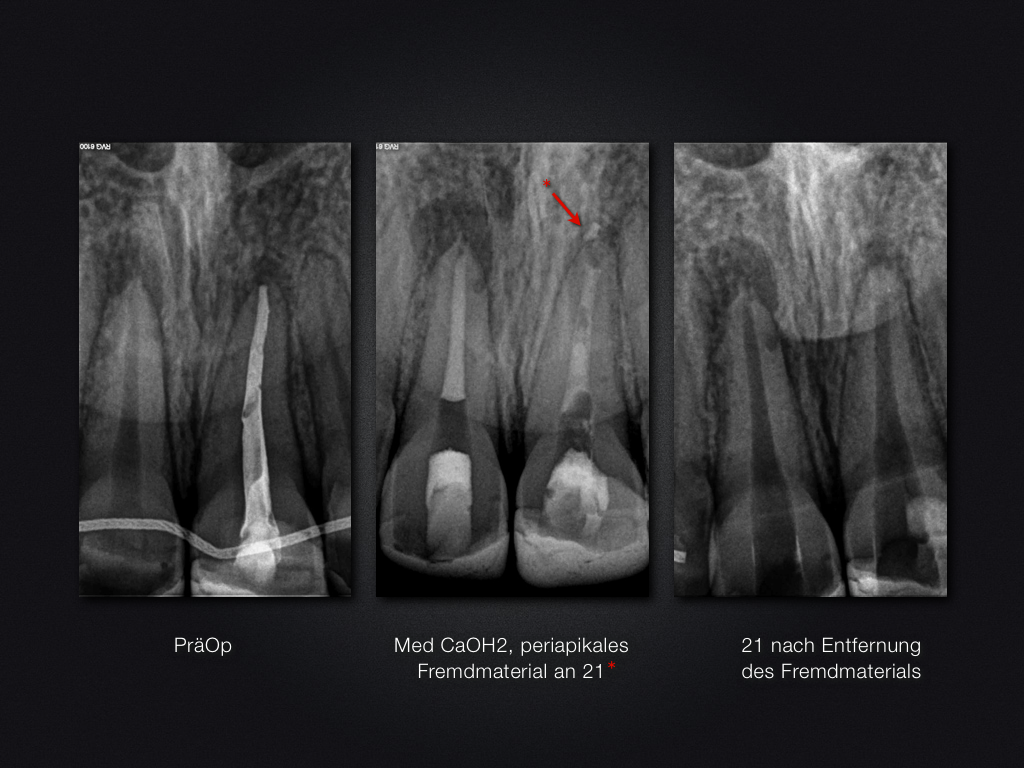

21 11D.016

Traumaspätfolge